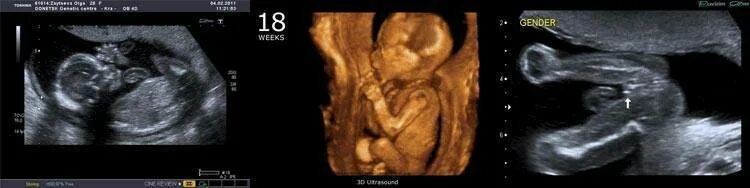

Как выглядит ребенок в 18 недель